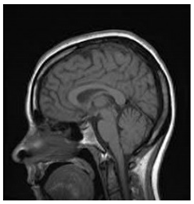

Table 1.

Results of marking and encrypting a medical image.

Table 1 shows the original image, marked image, encrypted image, the decrypted image, and the correlation between extracted blocks and original blocks after decryption using the Double Random Phase Encryption. It is clear that the encryption increases the security, and the mean correlation between the recovered mark and the original mark is measured to be 0.9 in both cases.

The PSNR and SSIM between the original image and marked image are 35.99 db and 0.97, respectively, which means that the marking does not affect the quality of the original image and keeps the invisibility of mark in the image. After encrypting the marked image using the DPRE algorithm, the results show that PSNR and SSIM between the encrypted and marked image are 12 db and 0.1, which verifies the strength of the suggested cryptosystem, as there is no similarity between them. Moreover, the results show that the correlation between the embedded rows and columns with the original is near to 1, verifying the robustness of the mark or signature.